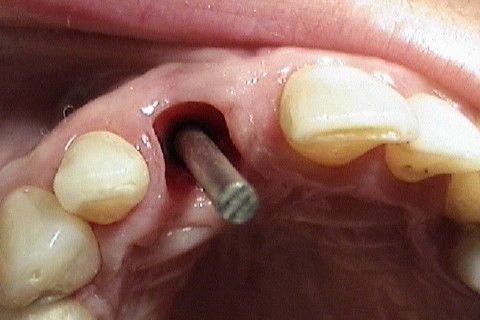

Implante colocado, com algumas expiras expostas e necessitando de enxerto